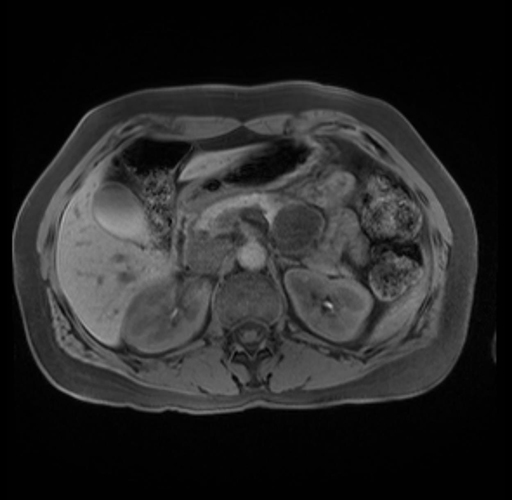

Imaging Analysis

Look through the patient's CT scan to identify any areas of concern for the necessary procedure.

Based on your CT findings, which issue(s) are present and would give reason for "planned slowing down moment(s)" in this case?